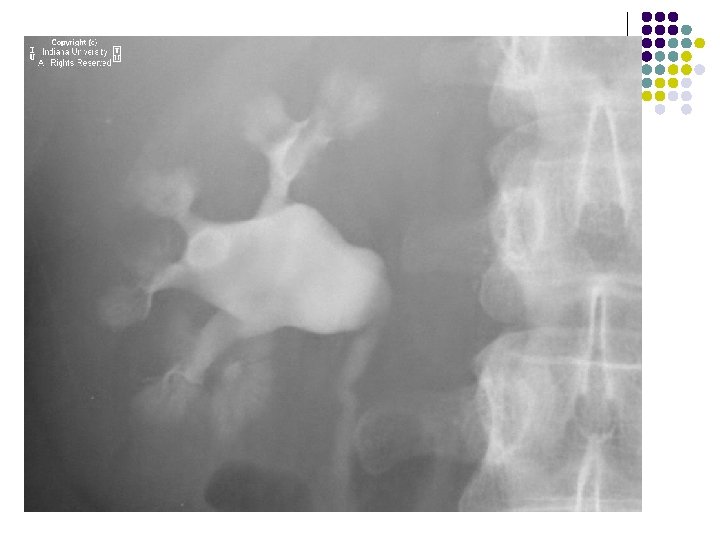

IMAGING FEATURES l Plain abdominal film: A well-defined right lower quadrant mass. l Contrast enema: Smooth indentation of the medial aspect of the cecum & non-opacification of the appendix. l Ultrasound: Completely anechoic or hypoechoic with variable internal echogenicity and Whorled appearance is characteristics due to internal contents May have posterior acoustic enhancement. with variable wall thickness and calcification.

FINDINGS l Supine AP radiograph of the abdomen reveals a normal abundant bowel gas pattern with no evidence of obstruction. l However, gas is seen within a small bowel loop in the right inguinal region. l Delayed supine AP images of the abdomen from a small bowel series demonstrates contrast within a small bowel loop within the right hemiscrotum.

RADIOLOGICAL FEATURES: ON PLAIN RADIOGRAPH: l A loop of air filled bowel will be seen outside the expected location of the abdomen/pelvis. l Occasionally, bowel will be visualized within the scrotum. l Further imaging is usually not needed. SMALL BOWEL FOLLOW THROUGH: l Contrast within a small bowel loop in the right inguinal canal. l Ultrasound is the imaging modality of choice in adults. A loop of bowel demonstrating peristalsis within the inguinal canal is diagnostic. The exam is performed at rest and with the valsalva maneuver in order to diagnose easily reducible hernias.